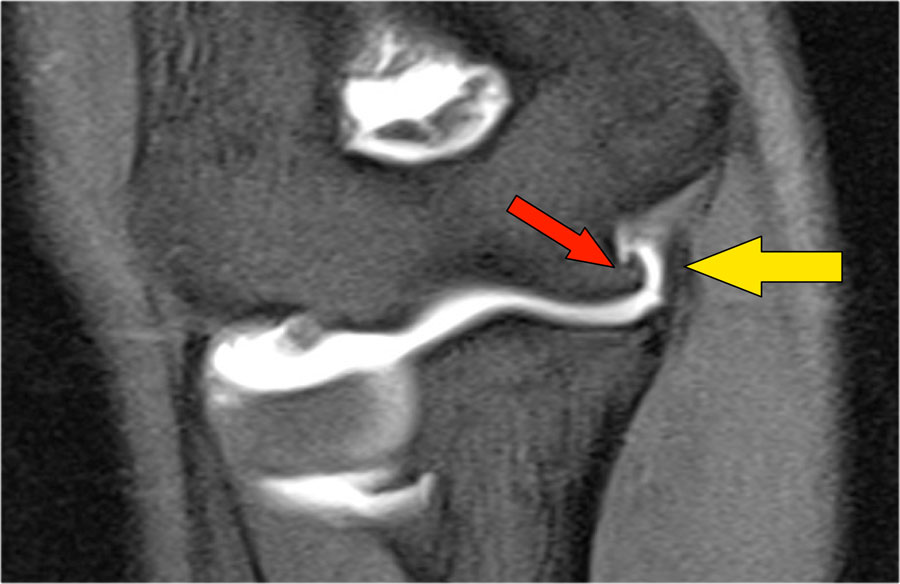

Plica

Cấu trúc này ở phía bên ngoài của khớp đôi khi được nhìn thấy và là một nếp gấp hoạt dịch (plica).

Nó có thể nổi bật và trông gần giống như một sụn chêm.

Đây là một cấu trúc bình thường, nhưng đôi khi nó bị dày lên hoặc không đều và có thể là nguyên nhân gây ra các triệu chứng.